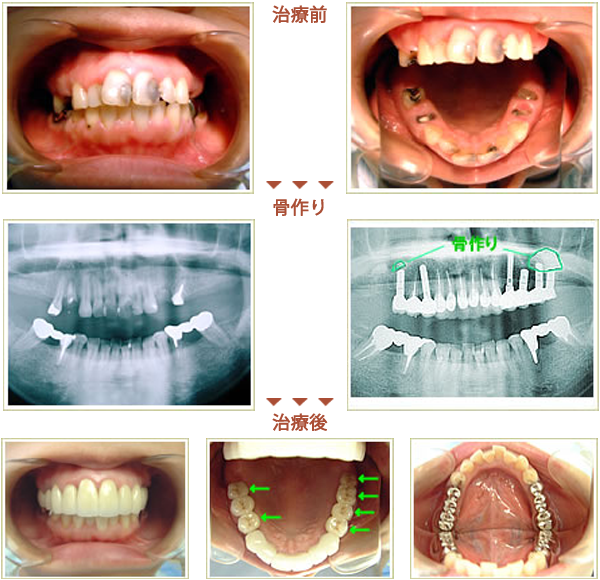

骨作りを行った症例

症例 38歳 女性 インプラント埋入数:6本